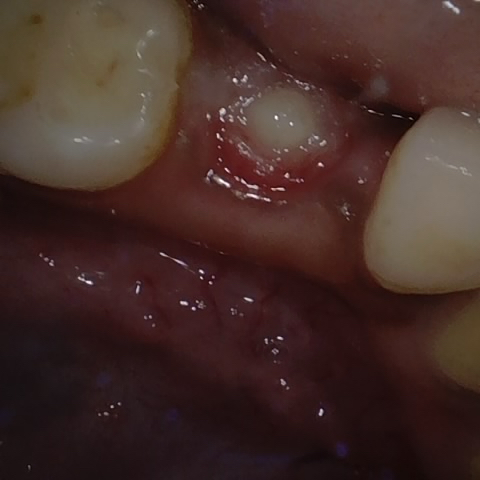

Image 1366 / 1715

NHD35761

Annotated as "Good"

Original Image Rendering Image